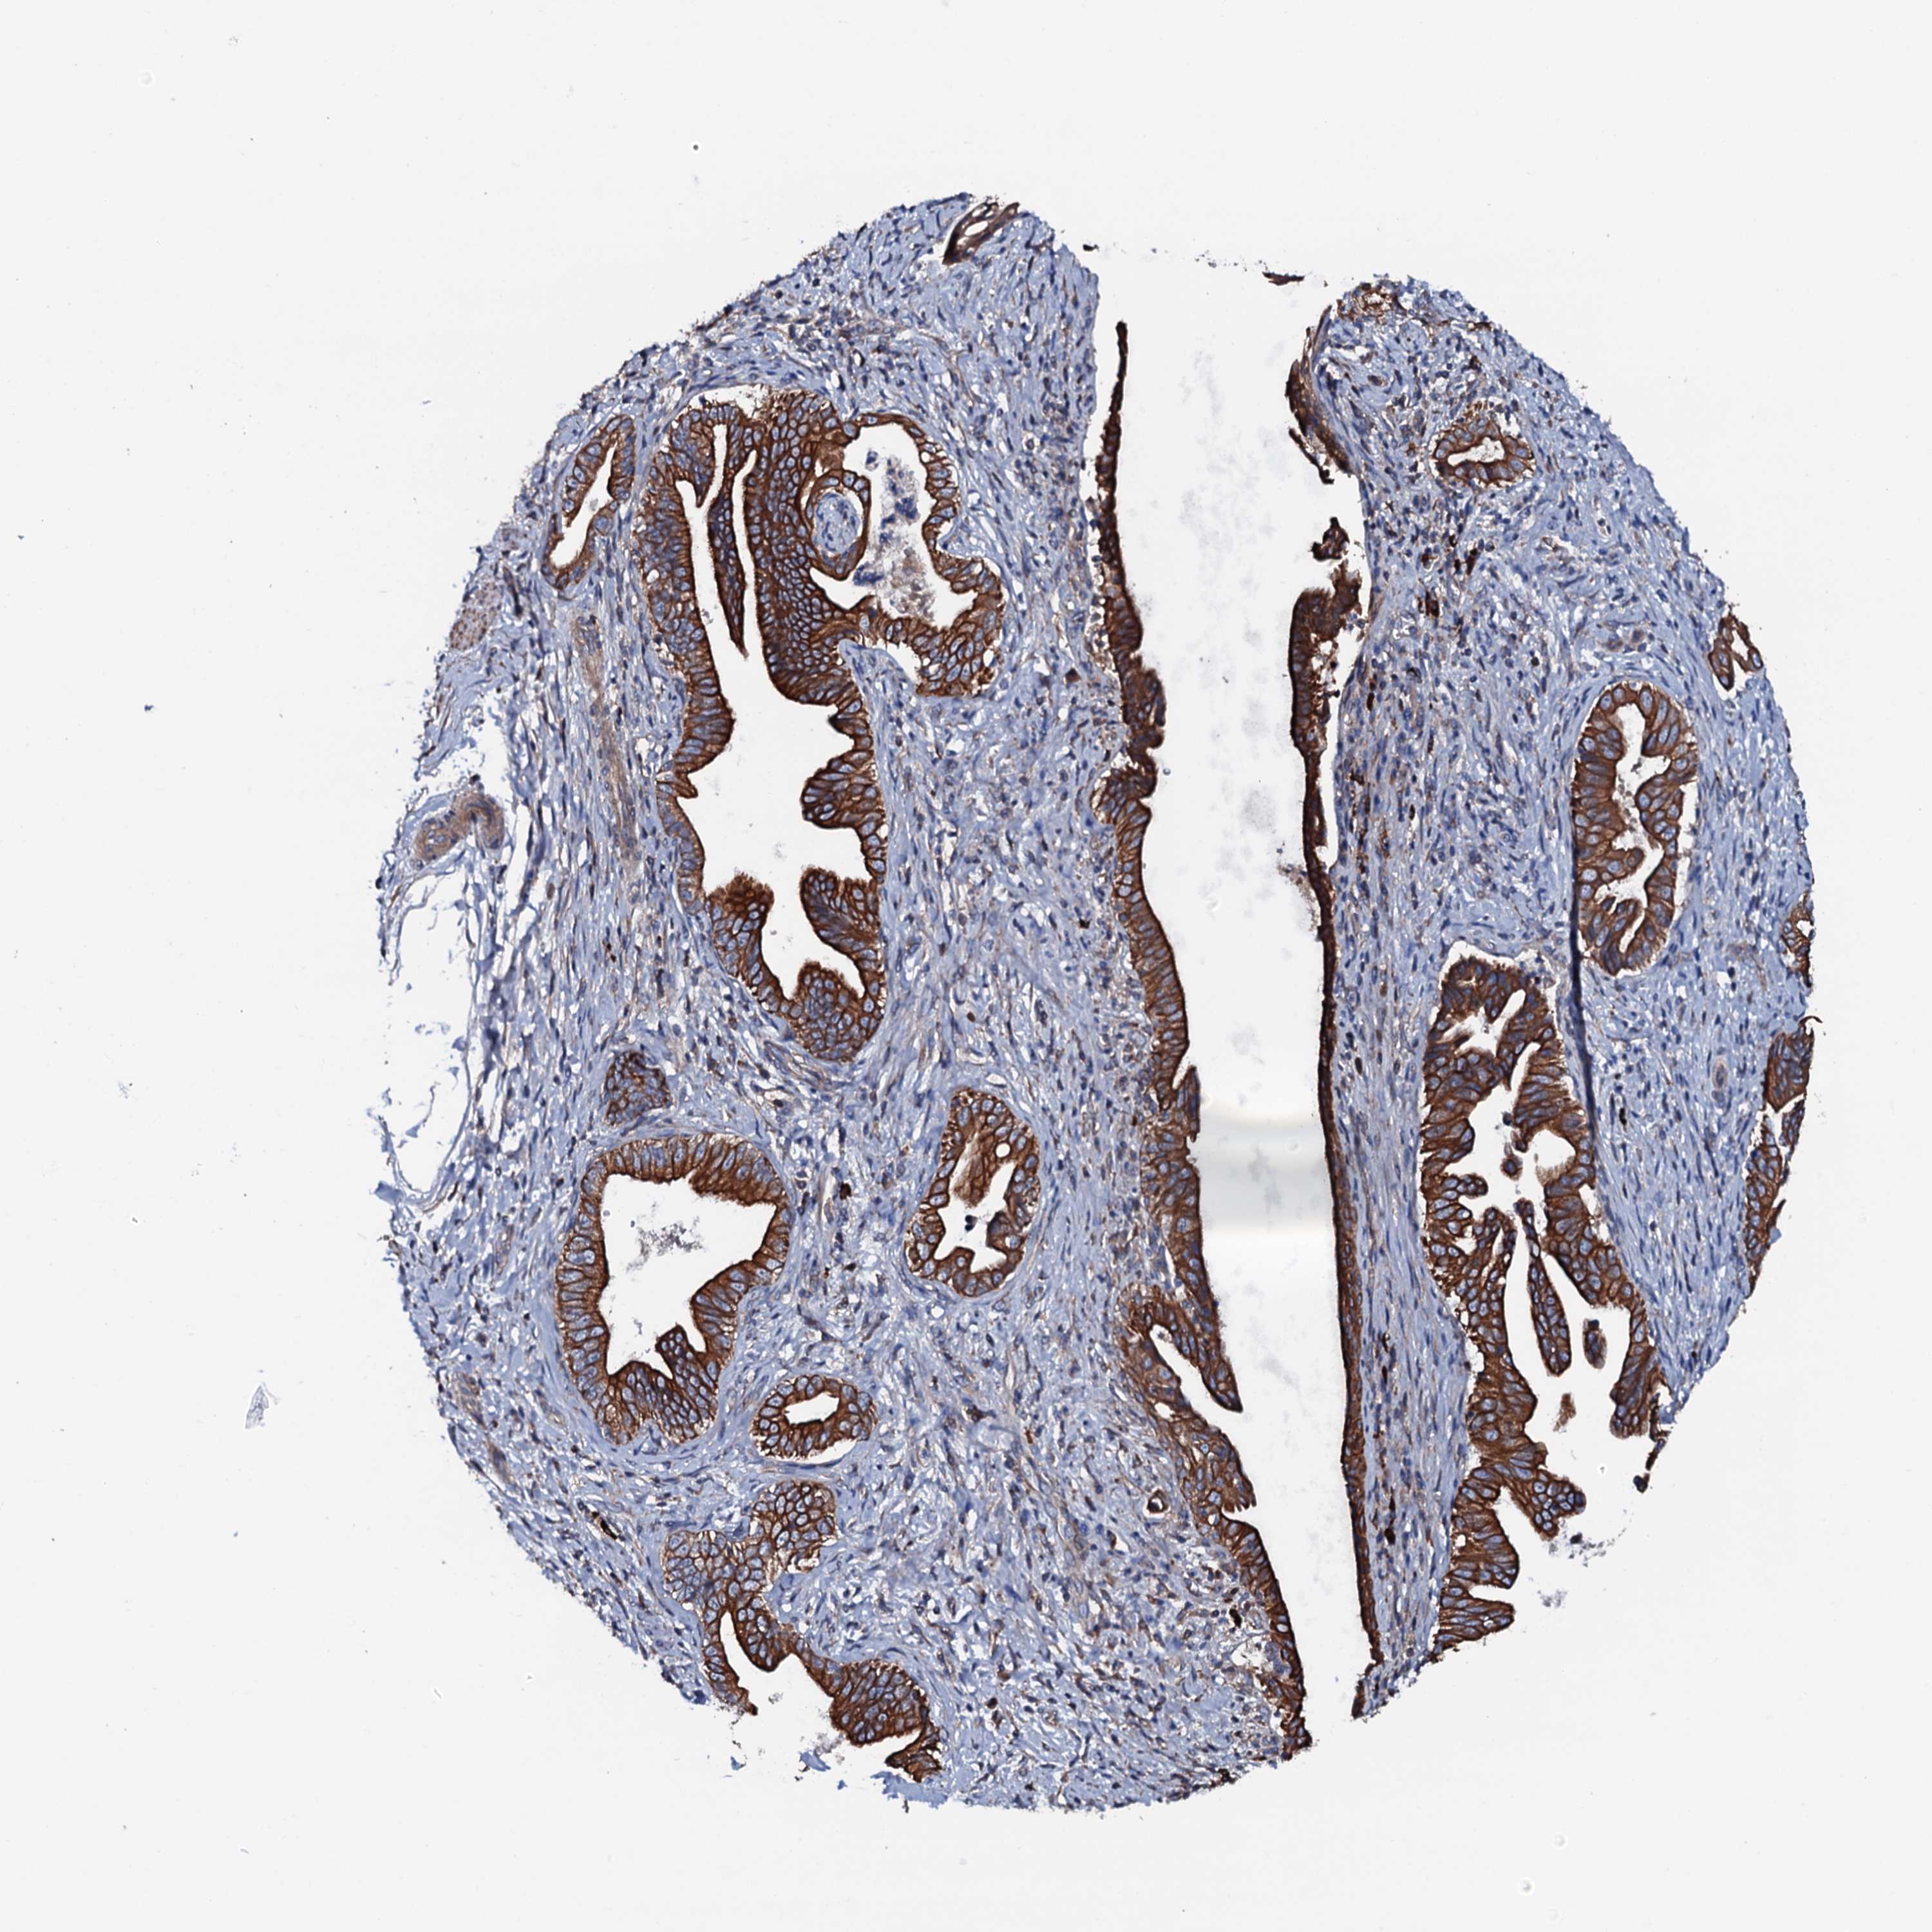

PANCREATIC CANCER - Protein expressioni

A mouse-over function shows sample information and annotation data. Click on an image to view it in a full screen mode. Samples can be filtered based on level of antibody staining by selecting one or several of the following categories: high, medium, low and not detected. The assay and annotation is described here.

Note that samples used for immunohistochemistry by the Human Protein Atlas do not correspond to samples in the TCGA dataset.

Antibody stainingi

Antibody staining in the annotated cell types in the current human tissue is reported as not detected, low, medium, or high, based on conventional immunohistochemistry profiling in selected tissues. This score is based on the combination of the staining intensity and fraction of stained cells.

Each image is clickable and will lead to virtual microscopy that enables deeper exploration of all samples and also displays staining intensity scores, fraction scores and subcellular localization as well as patient and tissue information for each sample.

Antibody HPA020873

Antibody HPA040413

Staining

High

Medium

Low

Not detected

Intensity

Strong

Moderate

Weak

Negative

Quantity

>75%

75%-25%

<25%

None

Location

Nuclear

Cytoplasmic/membranous

Cytoplasmic/membranous,nuclear

Adenocarcinoma, NOS